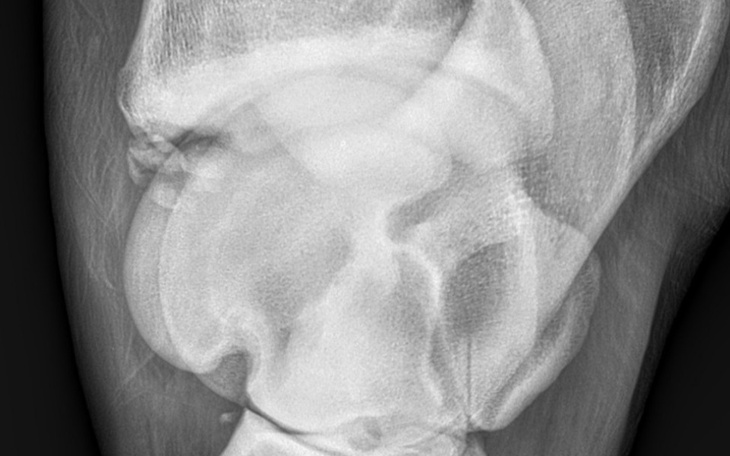

Jestem właścicielką trzyletniego wałacha niedawno koń zaczął kuleć po prześwietleniu które miał wykonane przez weterynarza okazało się że koń ma chipa odprysk kostny w stawie skokowym który musi być usunięty w klinice co niestety wiąże się z dużymi kosztami dlatego też prosimy o wsparcie. Bardzo zależy nam żeby koń mógł normalnie chodzić ponieważ znaczy dla nas bardzo wiele jest z nami odkąd skończył 7 miesięcy jest częścią naszej rodziny. Z góry bardzo dziękujemy wspierającym za pomoc .